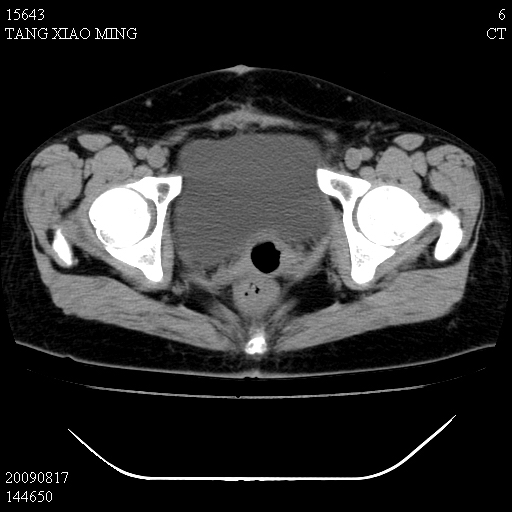

标题: CT21692:盆腔病变

女,33岁,右下腹痛2年余,既往宫外孕病史,如在我院手术,结果下周公布,

可能的诊断。1子宫内膜异位【子宫腺肌症并右卵巢巧克力囊肿】;2 右卵巢囊腺瘤。子宫肌瘤

1)考虑卵巢巧克力囊肿,不排除卵巢囊腺瘤。2)子宫肌瘤可能。

卵巢囊腺瘤,子宫肌瘤,直肠壁厚,不除外占位.